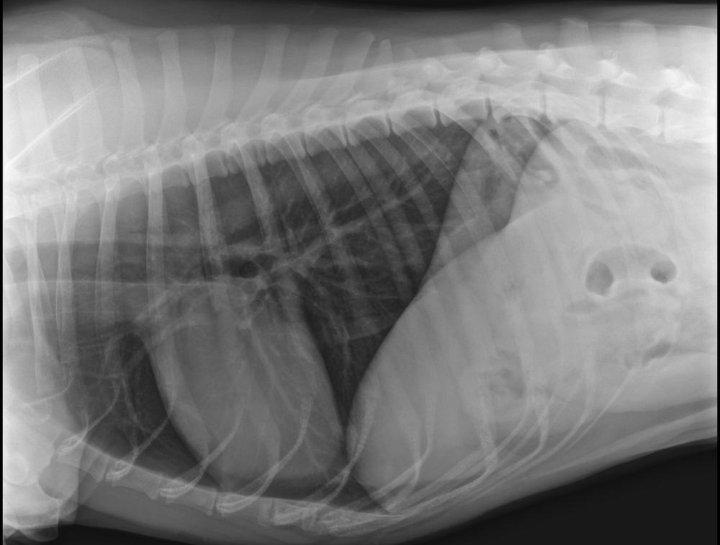

Pet Digital Radiology

Digital x-rays assist in diagnosing illness & injury.